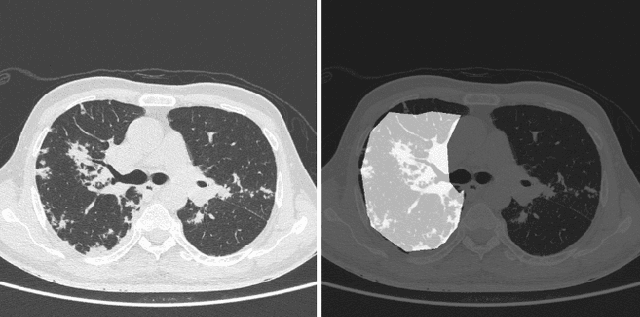

Abstract:Image segmentation plays a pivotal role in several medical-imaging applications by assisting the segmentation of the regions of interest. Deep learning-based approaches have been widely adopted for semantic segmentation of medical data. In recent years, in addition to 2D deep learning architectures, 3D architectures have been employed as the predictive algorithms for 3D medical image data. In this paper, we propose a 3D stack-based deep learning technique for segmenting manifestations of consolidation and ground-glass opacities in 3D Computed Tomography (CT) scans. We also present a comparison based on the segmentation results, the contextual information retained, and the inference time between this 3D technique and a traditional 2D deep learning technique. We also define the area-plot, which represents the peculiar pattern observed in the slice-wise areas of the pathology regions predicted by these deep learning models. In our exhaustive evaluation, 3D technique performs better than the 2D technique for the segmentation of CT scans. We get dice scores of 79% and 73% for the 3D and the 2D techniques respectively. The 3D technique results in a 5X reduction in the inference time compared to the 2D technique. Results also show that the area-plots predicted by the 3D model are more similar to the ground truth than those predicted by the 2D model. We also show how increasing the amount of contextual information retained during the training can improve the 3D model's performance.